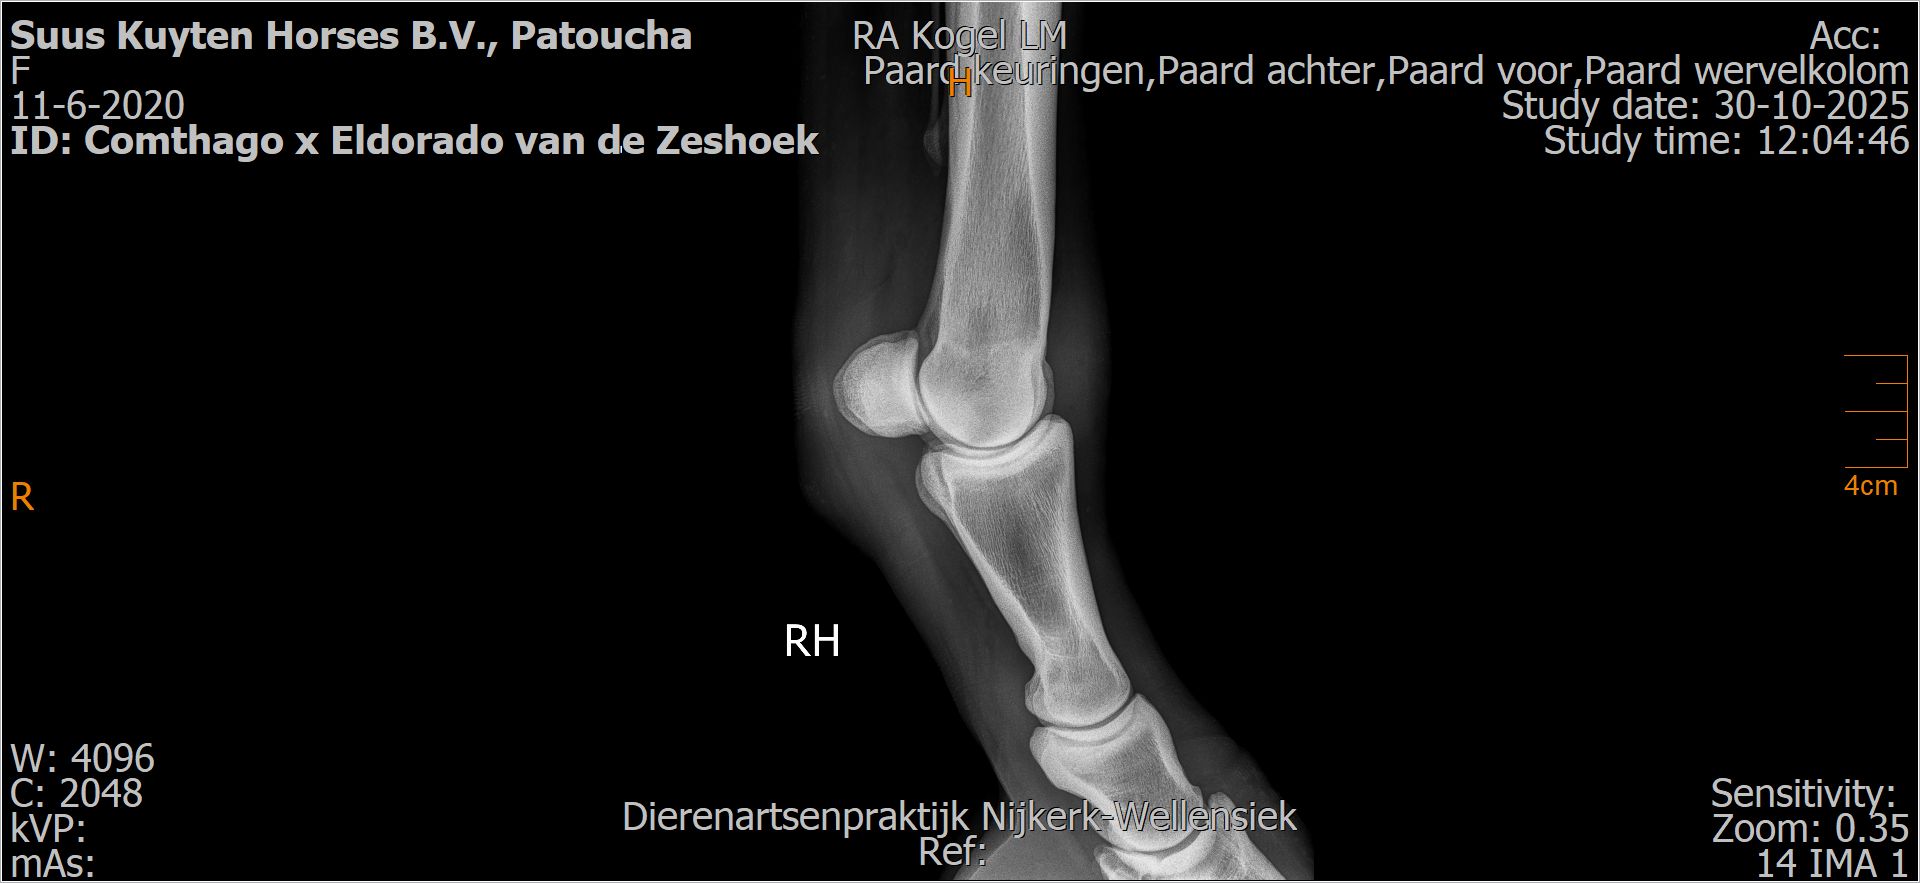

Patoucha

Leeftijd:

7

Röntgenfoto’s